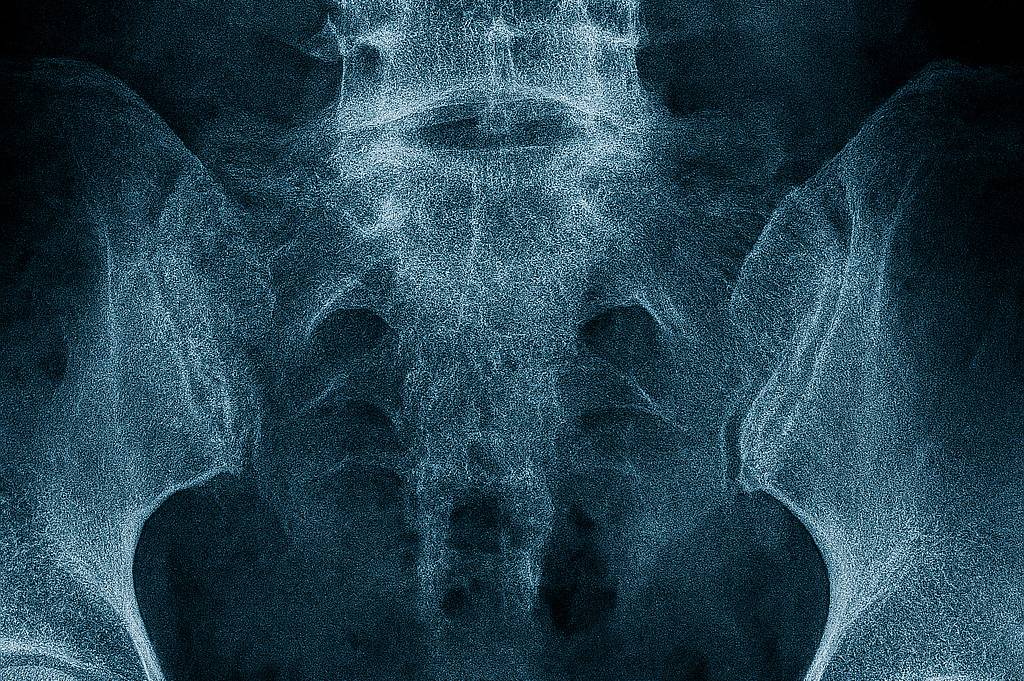

V počátečních fázích se osteoporóza nijak neprojevuje. Postupně se však mohou objevovat bolesti zad, zmenšování tělesné výšky, zakulacení páteře či časté zlomeniny po minimálním úrazu. Nejtypičtější jsou zlomeniny obratlů, zápěstí nebo krčku stehenní kosti.

Základem je denzitometrie (DXA) – bezbolestné vyšetření, které měří hustotu kostní hmoty. Lékař může doplnit laboratorní testy (hladina vápníku, vitaminu D, hormonů) a rentgenové snímky. Vyšetření se doporučuje zejména ženám po menopauze, mužům nad 65 let nebo lidem s rizikovými faktory.